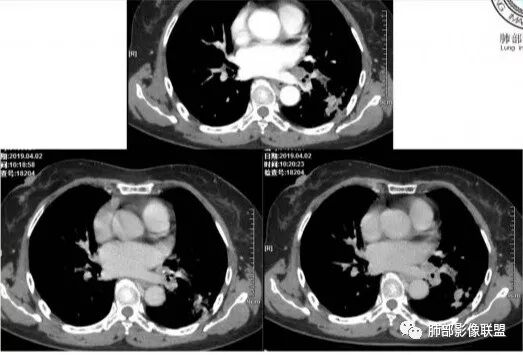

强化幅度太高了不是结核强化特点

左肺下叶多发结节影及磨玻璃影,抗感染病灶部分吸收,增强扫描速升速降,左肺门见环形强化淋巴结,病灶反反复复,考虑肺炎型肺癌。

这是老问题:1、肺门区软组织密度影较弥漫;我们常规鉴别的就是结核?鳞癌?既往我们群里基本这两方向。2、弥漫的淋巴结钙化,加上马赛克灌注。马赛克灌注的原因是两个,一个是肺动脉的,一个就是小气道的问题。我们看增强的区域,没有看到栓塞,所以我倾向于小气道的问题,就是弥漫气道病变,慢性气道病变要考虑。我怀疑有没有淀粉样变性累及气道壁改变的可能。淀粉样变性是一个继发性病变,结核也可以,粉尘也可以。

实变部分强化很明显,怎么解释合理呢

结核强化可以这样吗?

肉芽肿期强化明显

肉芽肿是一个病理的概念,是炎症后期的修复,它的本质其实是迟发型过敏反应引起的炎症,在免疫应答中主要是一些巨噬细胞、上皮细胞来起作用,但是里面有非常丰富的毛细血管,所以这类病变强化很明显,影像上一般是结节状、团块状、大片状,整体有膨隆,边缘也有收缩,肉芽肿是一大类,影像有时很难区分,尘肺、结节病、淋巴瘤样肉芽肿都可以。常见的是炎性的,多见于结核,细菌性感染后期引起的类似op样,影像统称肉芽肿类病变,鉴别炎性还是恶性,要根据边缘、形态、周围结构及内部坏死情况。

3.病灶强化比较明显。